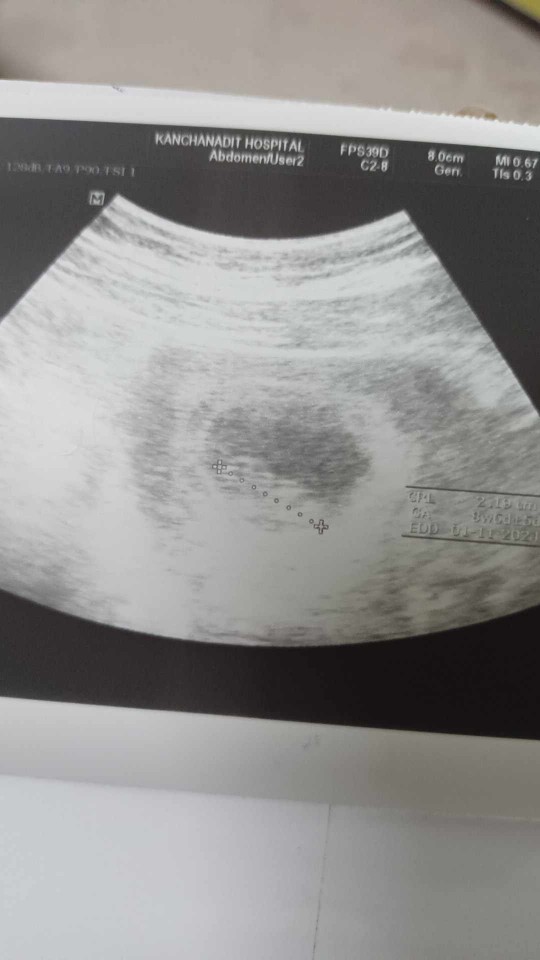

แม่ๆซาวด์เห็นตัวเด็กตอนกี่วีคบ้างคะ เราไปรอบแรกตอน6วีค ไม่เห็นอะไรเลย รอบล่าสุด9วีค ซาวด์เห็นแค่ถุงตามรูปเลยค่ะ เครียดมากเลยค่ะกลัวเป็นท้องลม #ซาวด์แค่หน้าท้องอย่างเดียวนะคะ